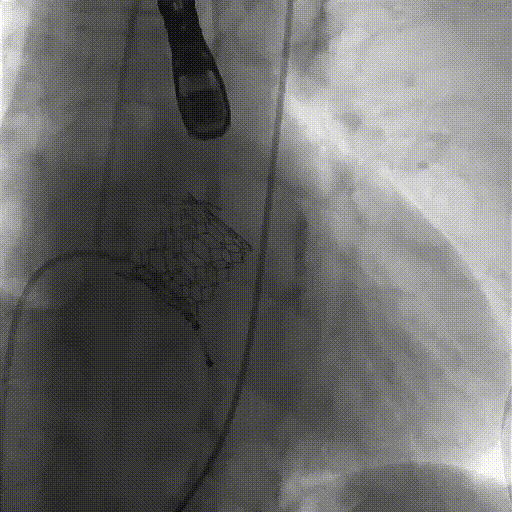

三个定位键定位于主动脉窦底,瓣膜自动定位于主动脉瓣口